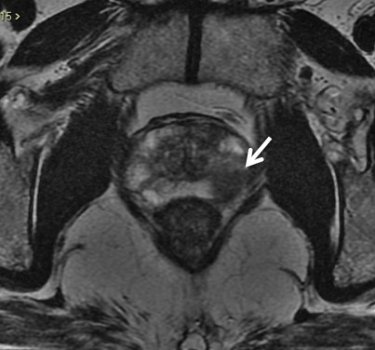

Figura 4. Imagem axial de RM da próstata ponderada em T2. Nódulo bem delimitado com baixo sinal na zona periférica esquerda, de alta probabilidade de neoplasia clinicamente significativa.

Este achado tem alta sensibilidade na detecção de câncer de próstata com valores de Gleason de 7 ou mais, porém não é específico, e pode ser encontrado em diversas condições, como prostatite, hemorragia, atrofia, cicatrizes e pós-tratamentos.15